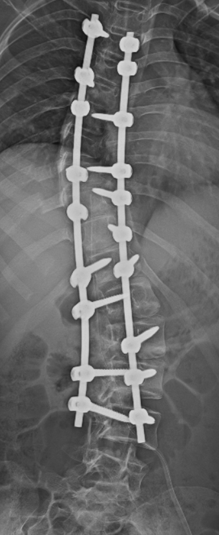

Scoliosis means your spine curves sideways. It can happen in children or adults and might require treatment if it is severe or causes pain.

We use rods and screws to stabilize the spine when needed, helping you move safely after injury or deformity.

We correct abnormal spine curves to improve posture, pain, and appearance.